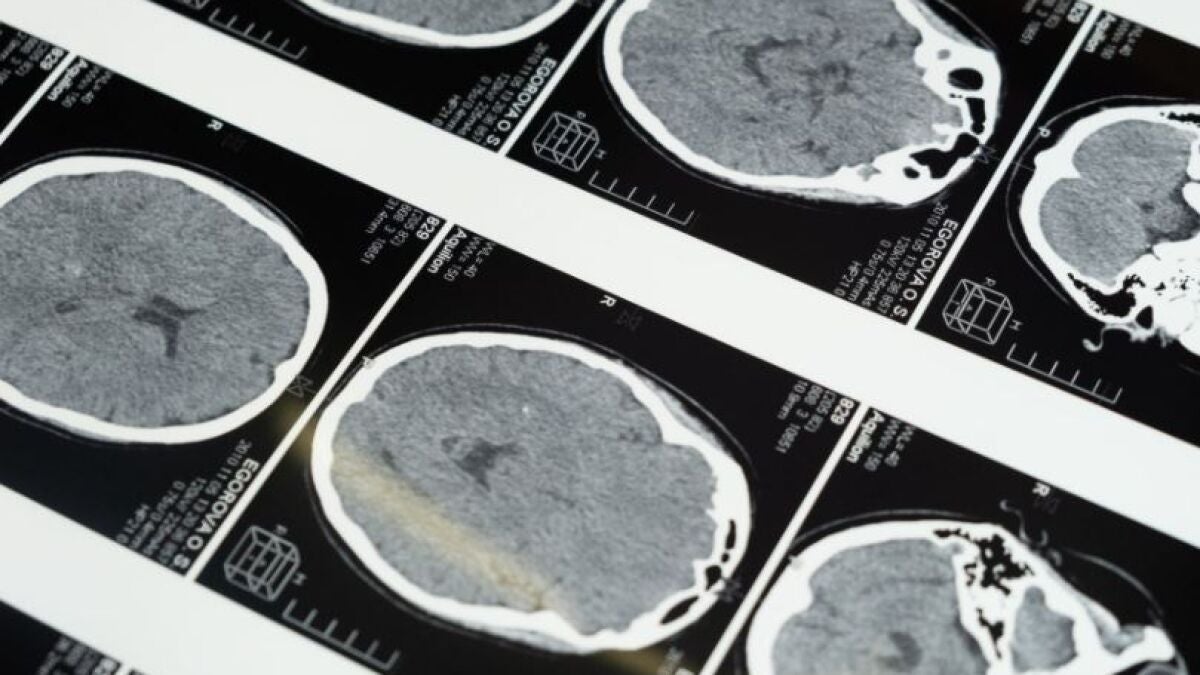

El ictus es una enfermedad que representa la segunda causa de muerte en España, la primera entre las mujeres. Se estima que una de cada seis personas, sufrirá un ictus a lo largo de su vida. Esto se produce cuando se da una obstrucción de una de las arterias que lleva la sangre a alguna zona del cerebro, ya sea una embolia o un trombo. Anualmente y solo en la Gerencia de Atención Integrada de Albacete se activa de media en 300 ocasiones el Código Ictus.

Además de este aspecto, se ha hablado del estado de la trombolisis y trombectomía mecánica, sobre la necesidad de una lectura de datos automatizada mediante un software específico de los estudios Tc multimodal o la creación del coordinador del Grupo Ictus.